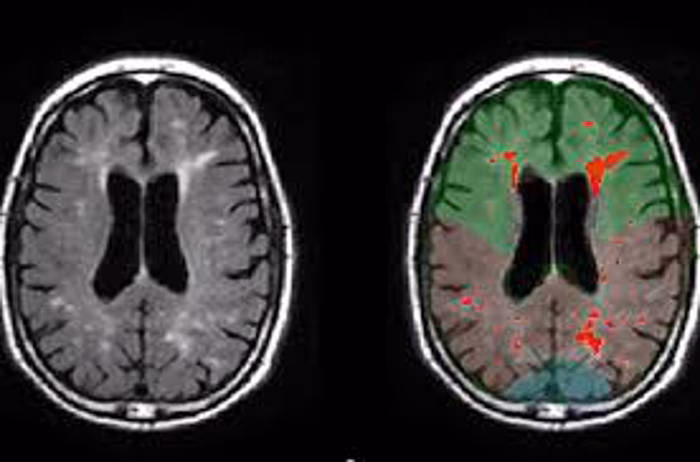

Las investigaciones que han explorado la actividad cerebral durante estados de profunda concentración espiritual, como la oración o la meditación, han identificado una red compleja de áreas cerebrales implicadas. El doctor Andrew Newberg, pionero en el uso de técnicas de neuroimagen para estudiar el cerebro en estos estados, ha señalado que múltiples estructuras trabajan conjuntamente.

El lóbulo frontal, por ejemplo, desempeña un papel crucial al permitirnos focalizar la atención y concentrarnos en la práctica, ya sea una oración o una meditación. El sistema límbico, conocido por su papel en las emociones, se activa y permite experimentar sentimientos intensos y poderosos asociados a la experiencia espiritual.

Quizás una de las áreas más interesantes implicadas sean los lóbulos parietales. Estas regiones del cerebro están involucradas en nuestra orientación espacial y temporal, así como en la construcción de nuestro sentido del yo, la distinción entre 'yo' y 'no-yo'. Newberg y otros investigadores han observado que, durante la meditación intensa o la oración profunda, la actividad en ciertas partes de los lóbulos parietales puede disminuir significativamente. Cuando se bloquea la entrada sensorial a esta región, como ocurre en la inmersión total de la meditación, el cerebro tiene dificultades para mantener la distinción entre el ser y el entorno. Esto puede llevar a una percepción de que el yo es ilimitado, íntimamente interconectado con todo lo demás, o a una sensación de unidad con el universo o con la divinidad. La falta de datos sensoriales en el lóbulo parietal derecho, en particular, parece correlacionarse con una sensación de espacio infinito.

Estas observaciones sugieren que las experiencias subjetivas de trascendencia, unidad o conexión profunda podrían estar vinculadas a patrones específicos de actividad (o inactividad) en redes neuronales concretas.